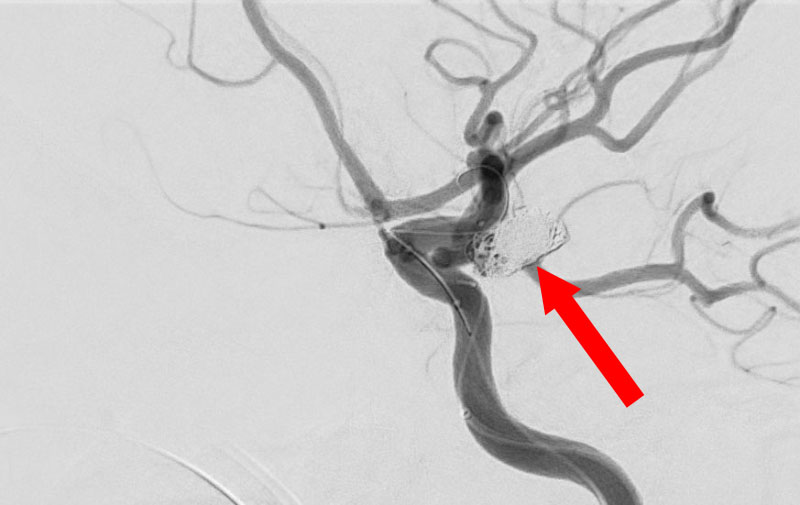

No.1596 手術後

くも膜下出血

左中大脳動脈瘤破裂

40代